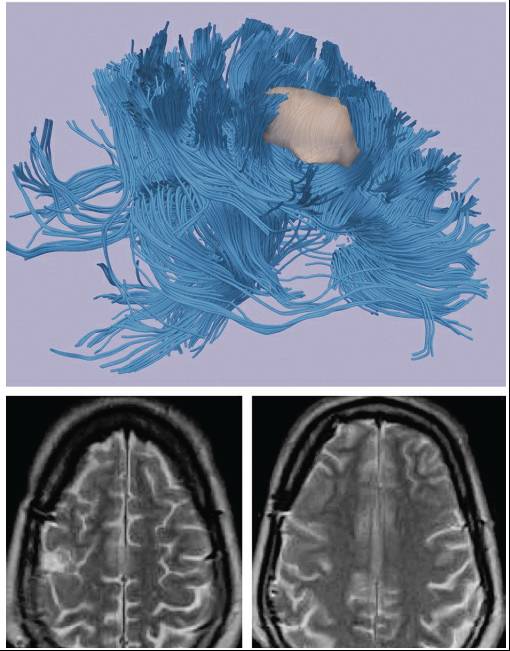

功能磁共振可以为手术计划提供重要的参考价值。它可以帮助明确病变和其相邻的重要皮层功能区之间的关系;但是对于靠近皮层功能区的肿瘤,它不能替代术中脑刺激神经电生理监测的作用。其它检查手段,如弥散张量磁共振成像(DTI)能够显示肿瘤周围的白质纤维束,还可以评估肿瘤的浸润程度。

图3. 紧靠运动皮层的低级别胶质瘤(上图)。功能磁共振和弥散张量磁共振成像显示病变紧靠重要纤维束,但是与其有清晰的边界(中图)。术中在神经电生理监测指导下进行病变全切除,并没有造成新的神经功能缺失(下图)。